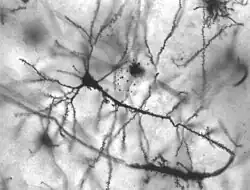

Transtornos neurobiológicos ou tanstornos neurológicos são as doenças do cérebro, coluna vertebral e nervos que as conectam. Existem mais de 600 doenças do sistema nervoso, tais como tumores cerebrais, epilepsia, doença de Parkinson, acidente vascular cerebral, bem como as menos conhecidas, como a demência frontotemporal.[1] Centenas de milhões de pessoas no mundo são afetadas por distúrbios neurológicos: por exemplo, 50 milhões de pessoas têm epilepsia; 62 milhões são afetados por doença cerebrovascular; 326 milhões de pessoas sofrem de enxaqueca; 24,5 milhões são afetados pela doença de Alzheimer e outras demências globalmente.[2]